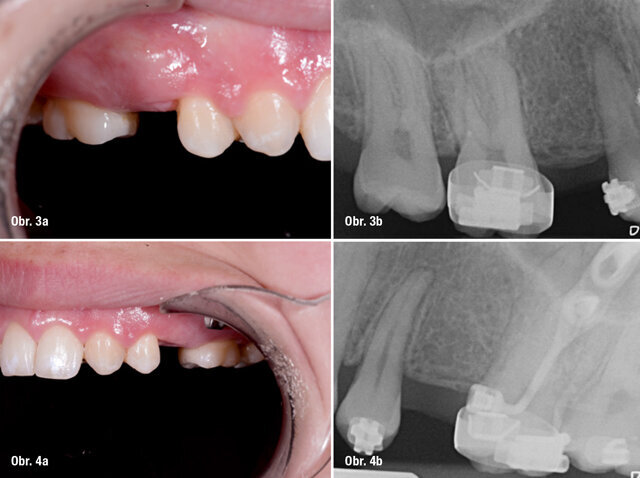

Předoperační snímek a boční fotografie oblasti 15 a 25

Pacientkou byla jednadvacetiletá žena, která se do zubní ordinace dostavila za účelem náhrady obou horních druhých premolárů, oblast 15 a 25. Pacientka byla v dobrém celkovém zdravotním stavu a nekuřačka. Dříve byla léčena na ortodontickém oddělení Univerzitní nemocnice v Gentu pro mnohočetné ageneze zubů. Intraorální vyšetření ukázalo nepřítomnost obou postranních řezáků a druhých premolárů v horní čelisti a obou druhých premolárů v dolní čelisti. Parodontologické vyšetření neprokázalo žádné známky patologie. Minišrouby pro skeletální kotvení během ortodontické léčby byly stále přítomny ve druhém a čtvrtém kvadrantu. Léčba vyžadovala zavedení dvou zubních implantátů v bezzubých oblastech horní čelisti. Oba implantáty měly být opatřeny provizorními korunkami během dvanácti hodin od zavedení implantátu (okamžité zatížení).

Před zákrokem byl sejmut otisk zubního oblouku pomocí ireverzibilního hydrokoloidu (Cavex CA37, fast set, CavexHolland) pro výrobu studijního modelu. Tento model byl použit pro výrobu chirurgické dlahy, dále jen NaviStent (obr. 1a, b). NaviStent sloužila jako skenovací šablona a byla také použita v průběhu chirurgického zákroku. Poté byla pacientka odeslána s nasazenou NaviStent na vyšetření CBCT (obr. 2; 3a, b; 4a, b).